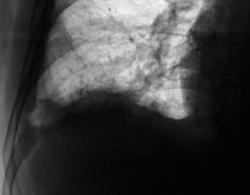

Пациент был направлен в рентгеновский кабинет терапевтом с диагнозом "Правостороняя пневмония". Было произведено стандартное исследование.

Было назначено противовоспалительное лечение. Через 1 неделю проведен "рентген-контроль".

правостороннего плеврального выпота в проекции средней доли.

Согласен с коллегой, но по-моему, кроме это выпот есть и заднем синусе. Картина в серия снимков №7-9, с небольшой положительной динамикой в сравнении данными в серии №4-6.

Кажущееся затемнение в области средней доли симулирует суперпозиция приподнятого правого купола диафрагмы и тени сердца. В заднем синусе справа - небольшой выпот, а со стороны диафрагмы, кроме элевации и выпрямления, присутствует картина диафрагматита в задних отделах. Вероятно необходимо ультразвуковое исследование органов брюшной полости и забрюшинного пространства для поиска первопричины данного состояния там. Динамика процесса за время наблюдения - явно положительная.